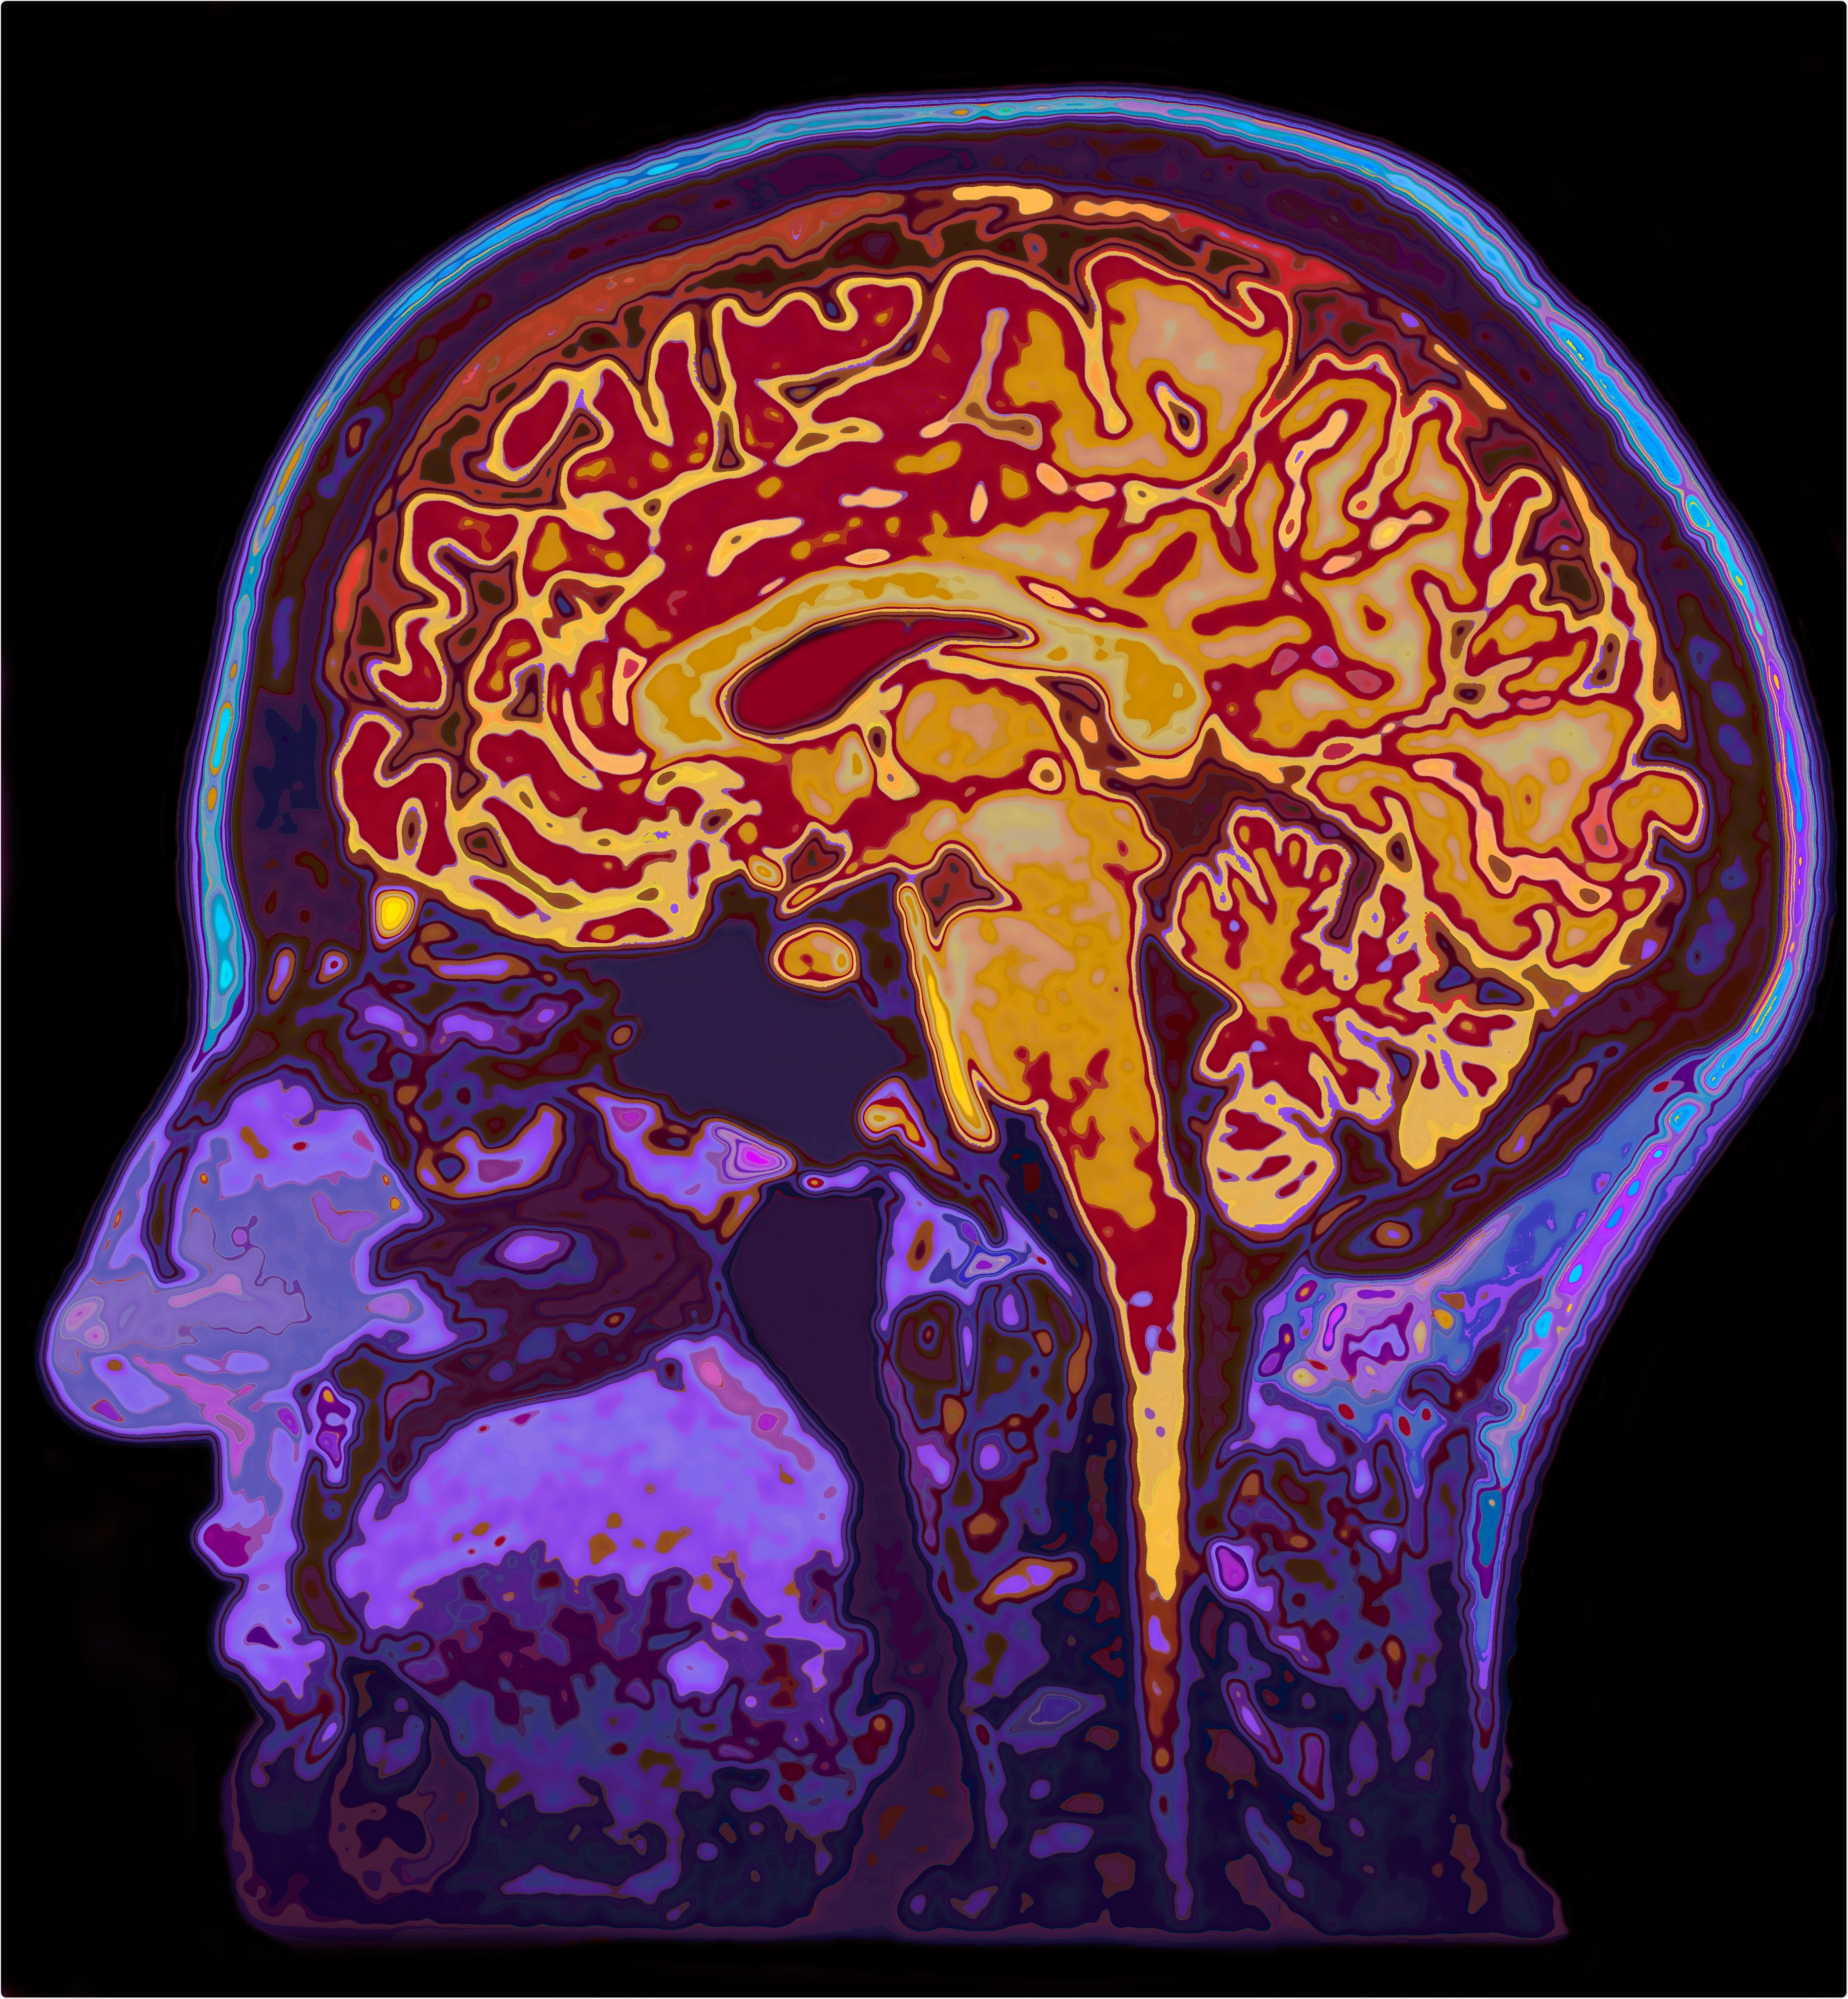

MRI Image of the human brain. Image Credit: SpeedKingz / Shutterstock